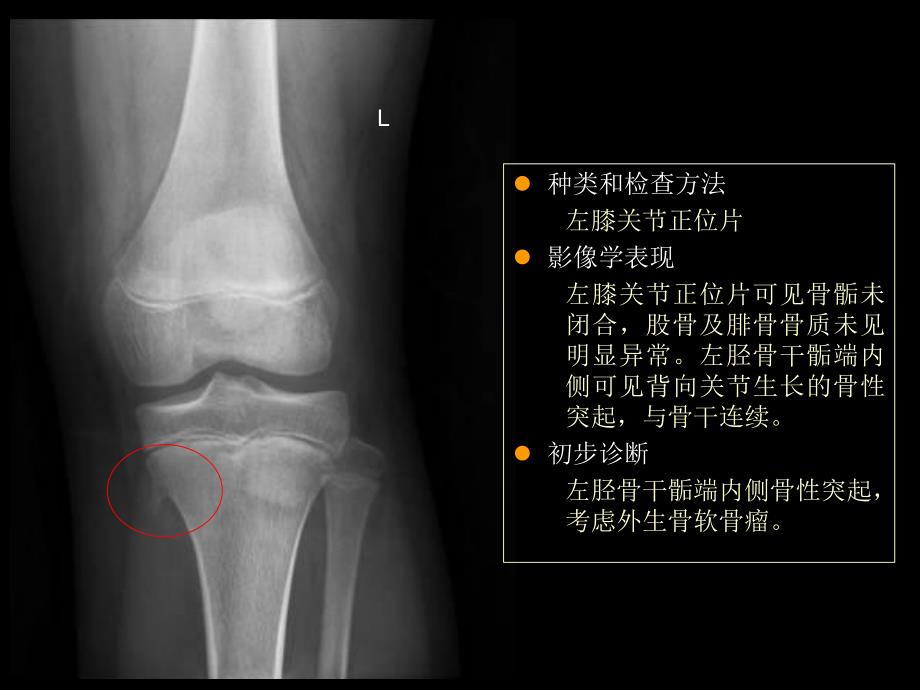

1、骨折及脱位移位判断l 以近端为准,判断远端移位方向和程度 l 移位和成角移位 骨折两端分离状况 成角 骨折两端长轴线平行状况l 良好的复位 对位 骨折端相接大于二分之一 对线 近端与远端长轴近似平行l 种类和检查方法左膝关节正位片l 影像学表现左膝关节正位片可见骨骺未闭合,股骨及腓骨骨质未见明显异常。左胫骨干骺端内侧可见背向关节生长的骨性突起,与骨干连续。l 初步诊断左胫骨干骺端内侧骨性突起,考虑外生骨软骨瘤。L髌骨轴位l 种类和检查方法左胫腓骨正侧位l 影像学表现左胫骨骨干下段见螺旋型透亮线,骨皮质连续性中断,断端移位和成角不明显。所见踝关节在位。腓骨骨质未见明显异常。l 初步诊断左胫骨下段